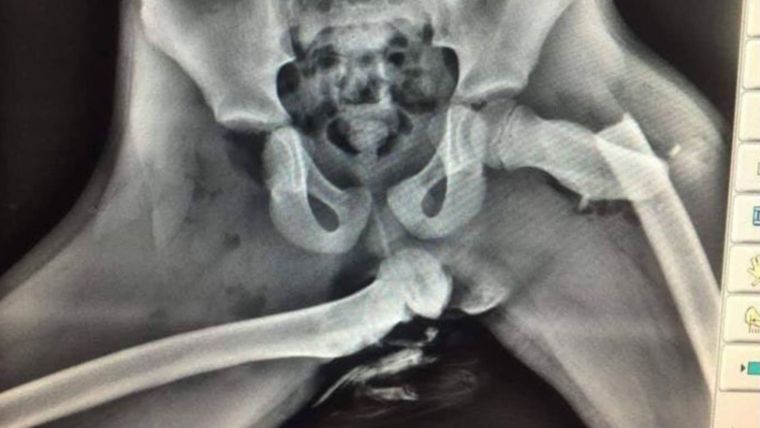

Para concientizar al público en general, ya que la imagen fue publicada en Twitter, la policía del distrito de Dyfed-Powys en Gales compartió esta imagen que pertenece a una radiografía de una víctima de un siniestro automovilístico.

Allí se puede ver la rotura de distintos huesos de la pierna como el fémur, causado justamente por tener colocado los pies en el tablero. Al parecer, en pleno accidente se accionó el airbag y esto hizo de prensa hacia las frágiles piernas de un niño menor de edad.

“Aquí hay una radiografía de horribles lesiones sufridas al pasajero del asiento delantero que tenía los pies en el tablero de instrumentos en el momento de una colisión. Si ve que su pasajero lo hace, deje de conducir y muéstrele esto”, describió en redes sociales uno de los oficiales de policía.